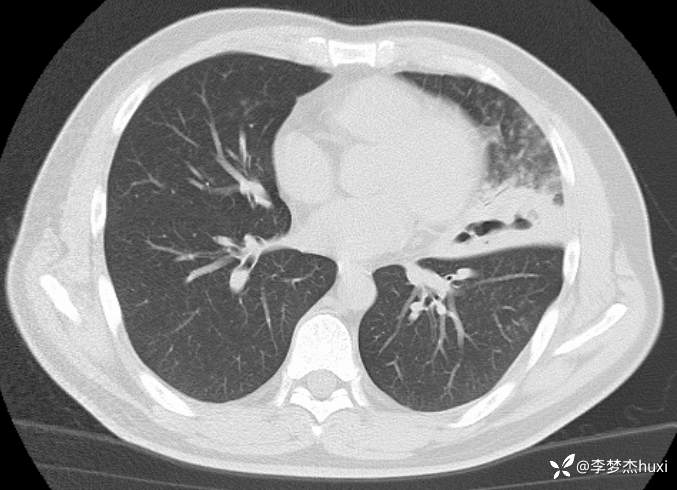

【现病史及既往史】: 1.患者中年 男,患者缘于5天前前无诱因出现咳嗽、咳痰,为黄痰,伴臭味,痰不易咳出,伴发热,最高体温不详,无喘息、憋气,无胸痛,无咯血,无腹痛腹泻,无恶心、呕吐。院外未应用药物治疗,症状无明显好转,为求进一步治疗来院就诊,门诊查胸部CT;双肺炎症,左肺上叶厚壁空洞形成,双肺纹理增重,双侧胸膜局限性增厚,脂肪肝,建议结合临床复查。以“肺炎”收住院;。

【临床诊断】:肺脓肿伴有肺炎。